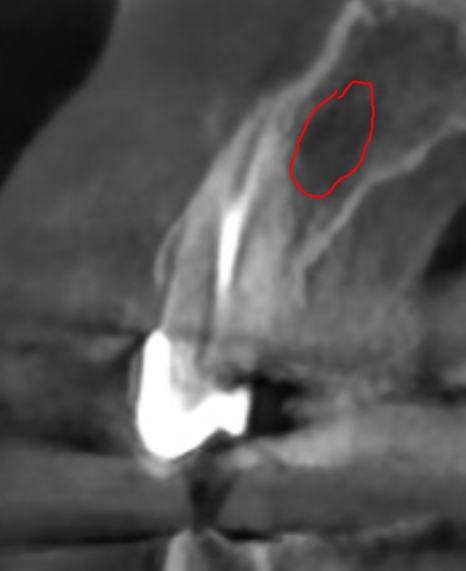

방사선 사진과 CT를 확인해보니

오래된 보철물 안쪽으로

2차 충치가 심하게 진행되어 있었고,

240315

특히 왼쪽 송곳니(#23)는 이미 치아 머리 부분이

부러져 뿌리와 분리된 상태였습니다.

뿌리 끝까지 염증이 퍼져

잇몸뼈가 많이 녹아있었기에,

안타깝게도 발치를 진행하기로 했습니다.